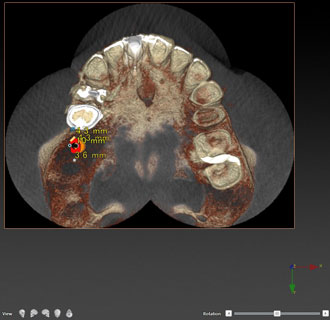

インプラント シュミレーション画像1

インプラント シュミレーション画像2

インプラント治療や、埋もれている歯の抜歯、口腔内の手術などを行う場合には、まずコンピューターでシミュレーションを行います。

CT画像をノーベルクリニシャン®︎で処理することで、様々な角度から画像を分析することが可能です。ノーベルクリニシャン®︎を使用する事で、より安全な治療が可能となりました。